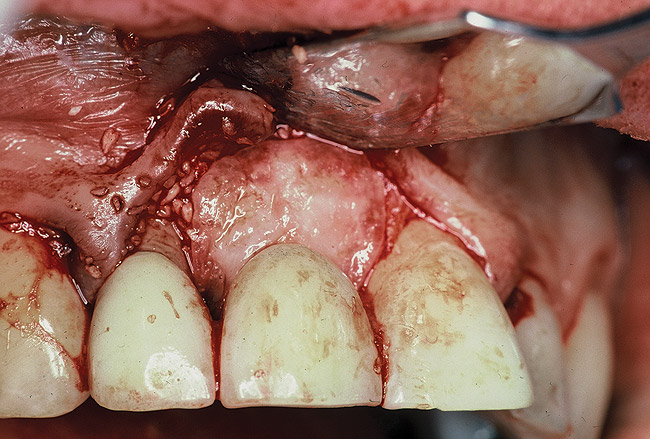

A 46-year-old man with an unremarkable medical history was referred for evaluation and treatment of the maxillary right central incisor implant. The implant, which had been placed 6 years prior, had never caused any problems until recently, when the patient noted both swelling and soreness at the site. Following 10 days of amoxicillin 500 mg tid, purulence was still present upon palpation of the tissue, and the patient was referred for consultation (Figure 6). Probing attachment loss of 10 mm on the distal aspect and 5 mm on the mesial were measured around the implant. Bone loss was advanced on the periapical radiograph at both the mesial and distal aspects of the hydroxyapatite-coated implant (Figure 7). Full-thickness facial and lingual flaps were reflected to access the implant and surrounding bone, with care taken to preserve the papilla. The defects around the implant on the mesial and distal were 1-wall, and bone loss was present on the direct facial and palatal aspects as well (Figure 8). The surface of the implant was decontaminated, followed by application of enamel matrix derivative. The lesion was filled with freeze-dried bone allograft (Figure 9). The graft-biologic was covered by a flowable polymer barrier (Figure 10). The flaps were coronally advanced and secured with monofilament sutures (Figure 11). The patient was prescribed amoxicillin with clavulanic acid and an oral rinse of 0.12% chlorhexidine during the post-operative period. The healing progressed uneventfully, achieving both a favorable soft-tissue profile and substantial bone fill, as determined radiographically. These results were stable for 7 years (Figure 12 and Figure 13).

Figure 9: Following implant surface decontamination and enamel matrix derivative applications, the defect was filled with a mineralized allograft combined with a biologic.

Figure 9